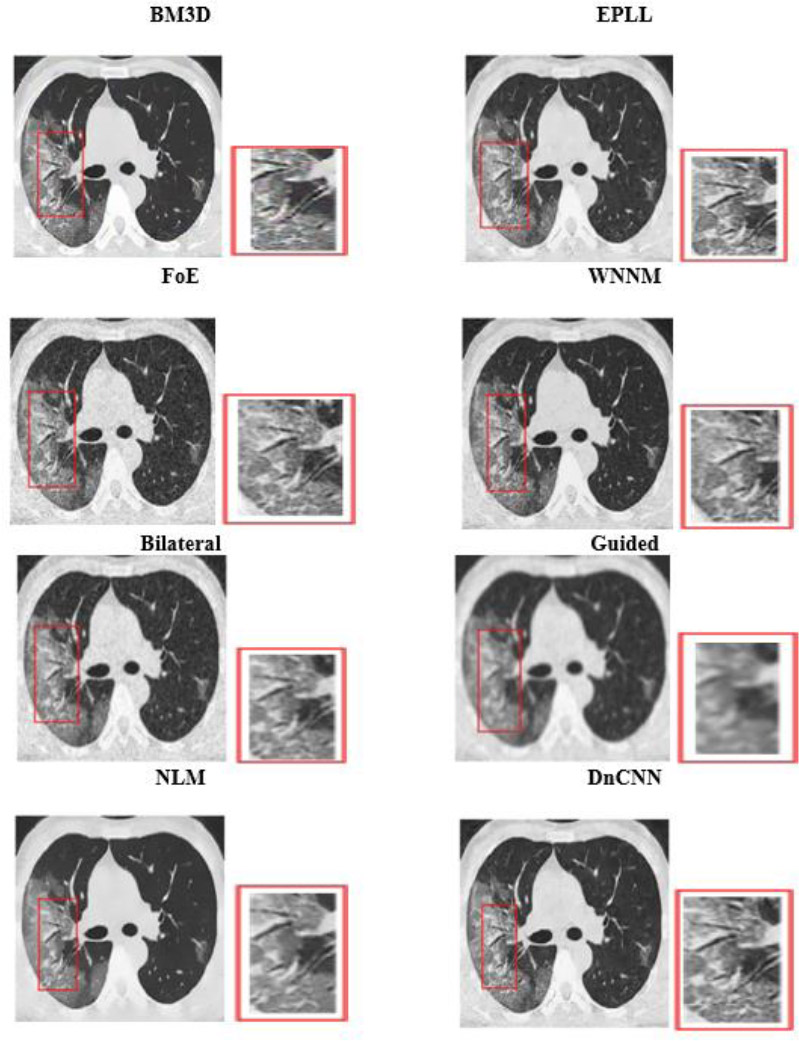

Visual analysis of the usual MRI and HRCT images is used to examine the qualitative performance of each denoising algorithm. Special attention was paid to anatomically relevant sites, such as fine pulmonary textures in HRCT and gray-white matter boundaries in T1-weighted brain MRI.

Run-time evaluation of different denoising algorithms.

The visual quality of the denoised images was determined on cropped and zoomed regions of interest (ROIs). The capability of the algorithms to minimize noise while preserving the most essential features, such as tumor borders, ventricular boundaries, or alveolar boundaries, was tested. Such an analysis is crucial, especially in medical imaging, where even slight degradation or excessive smoothing may obscure diagnostic clues. Perceived quality and artifact suppression are illuminated by visual comparisons, and quantitative measurements are corroborated.